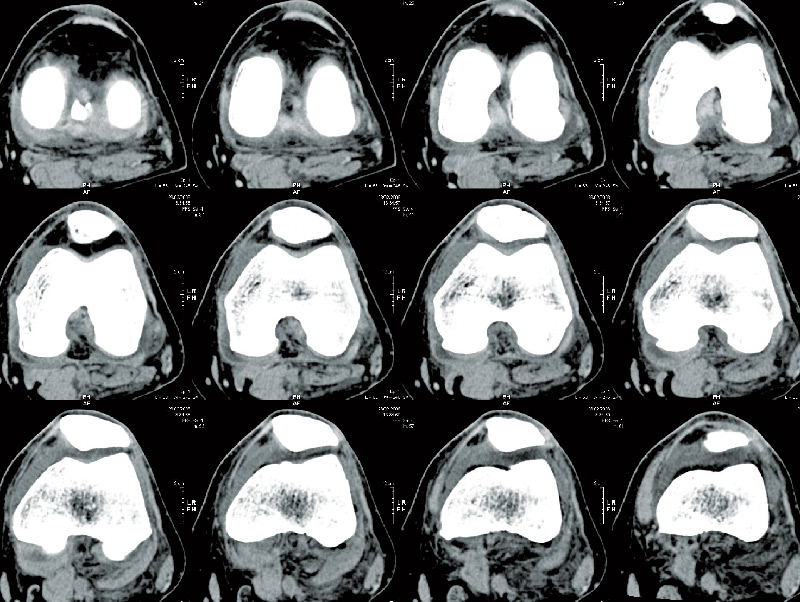

Πριν την εγχείρηση

Όλα ξεκινούν με μια αξονική τομογραφία (CT) της άρθρωσης του γόνατος η οποία χρησιμοποιείται για τη δημιουργία ενός εξατομικευμένου τρισδιάστατου εικονικού μοντέλου.

Αυτό το εικονικό μοντέλο φορτώνεται στο λογισμικό του συστήματος MAKO και χρησιμοποιείται από τον χειρουργό για να δημιουργήσει το εξατομικευμένο προ-εγχειρητικό πλάνο.